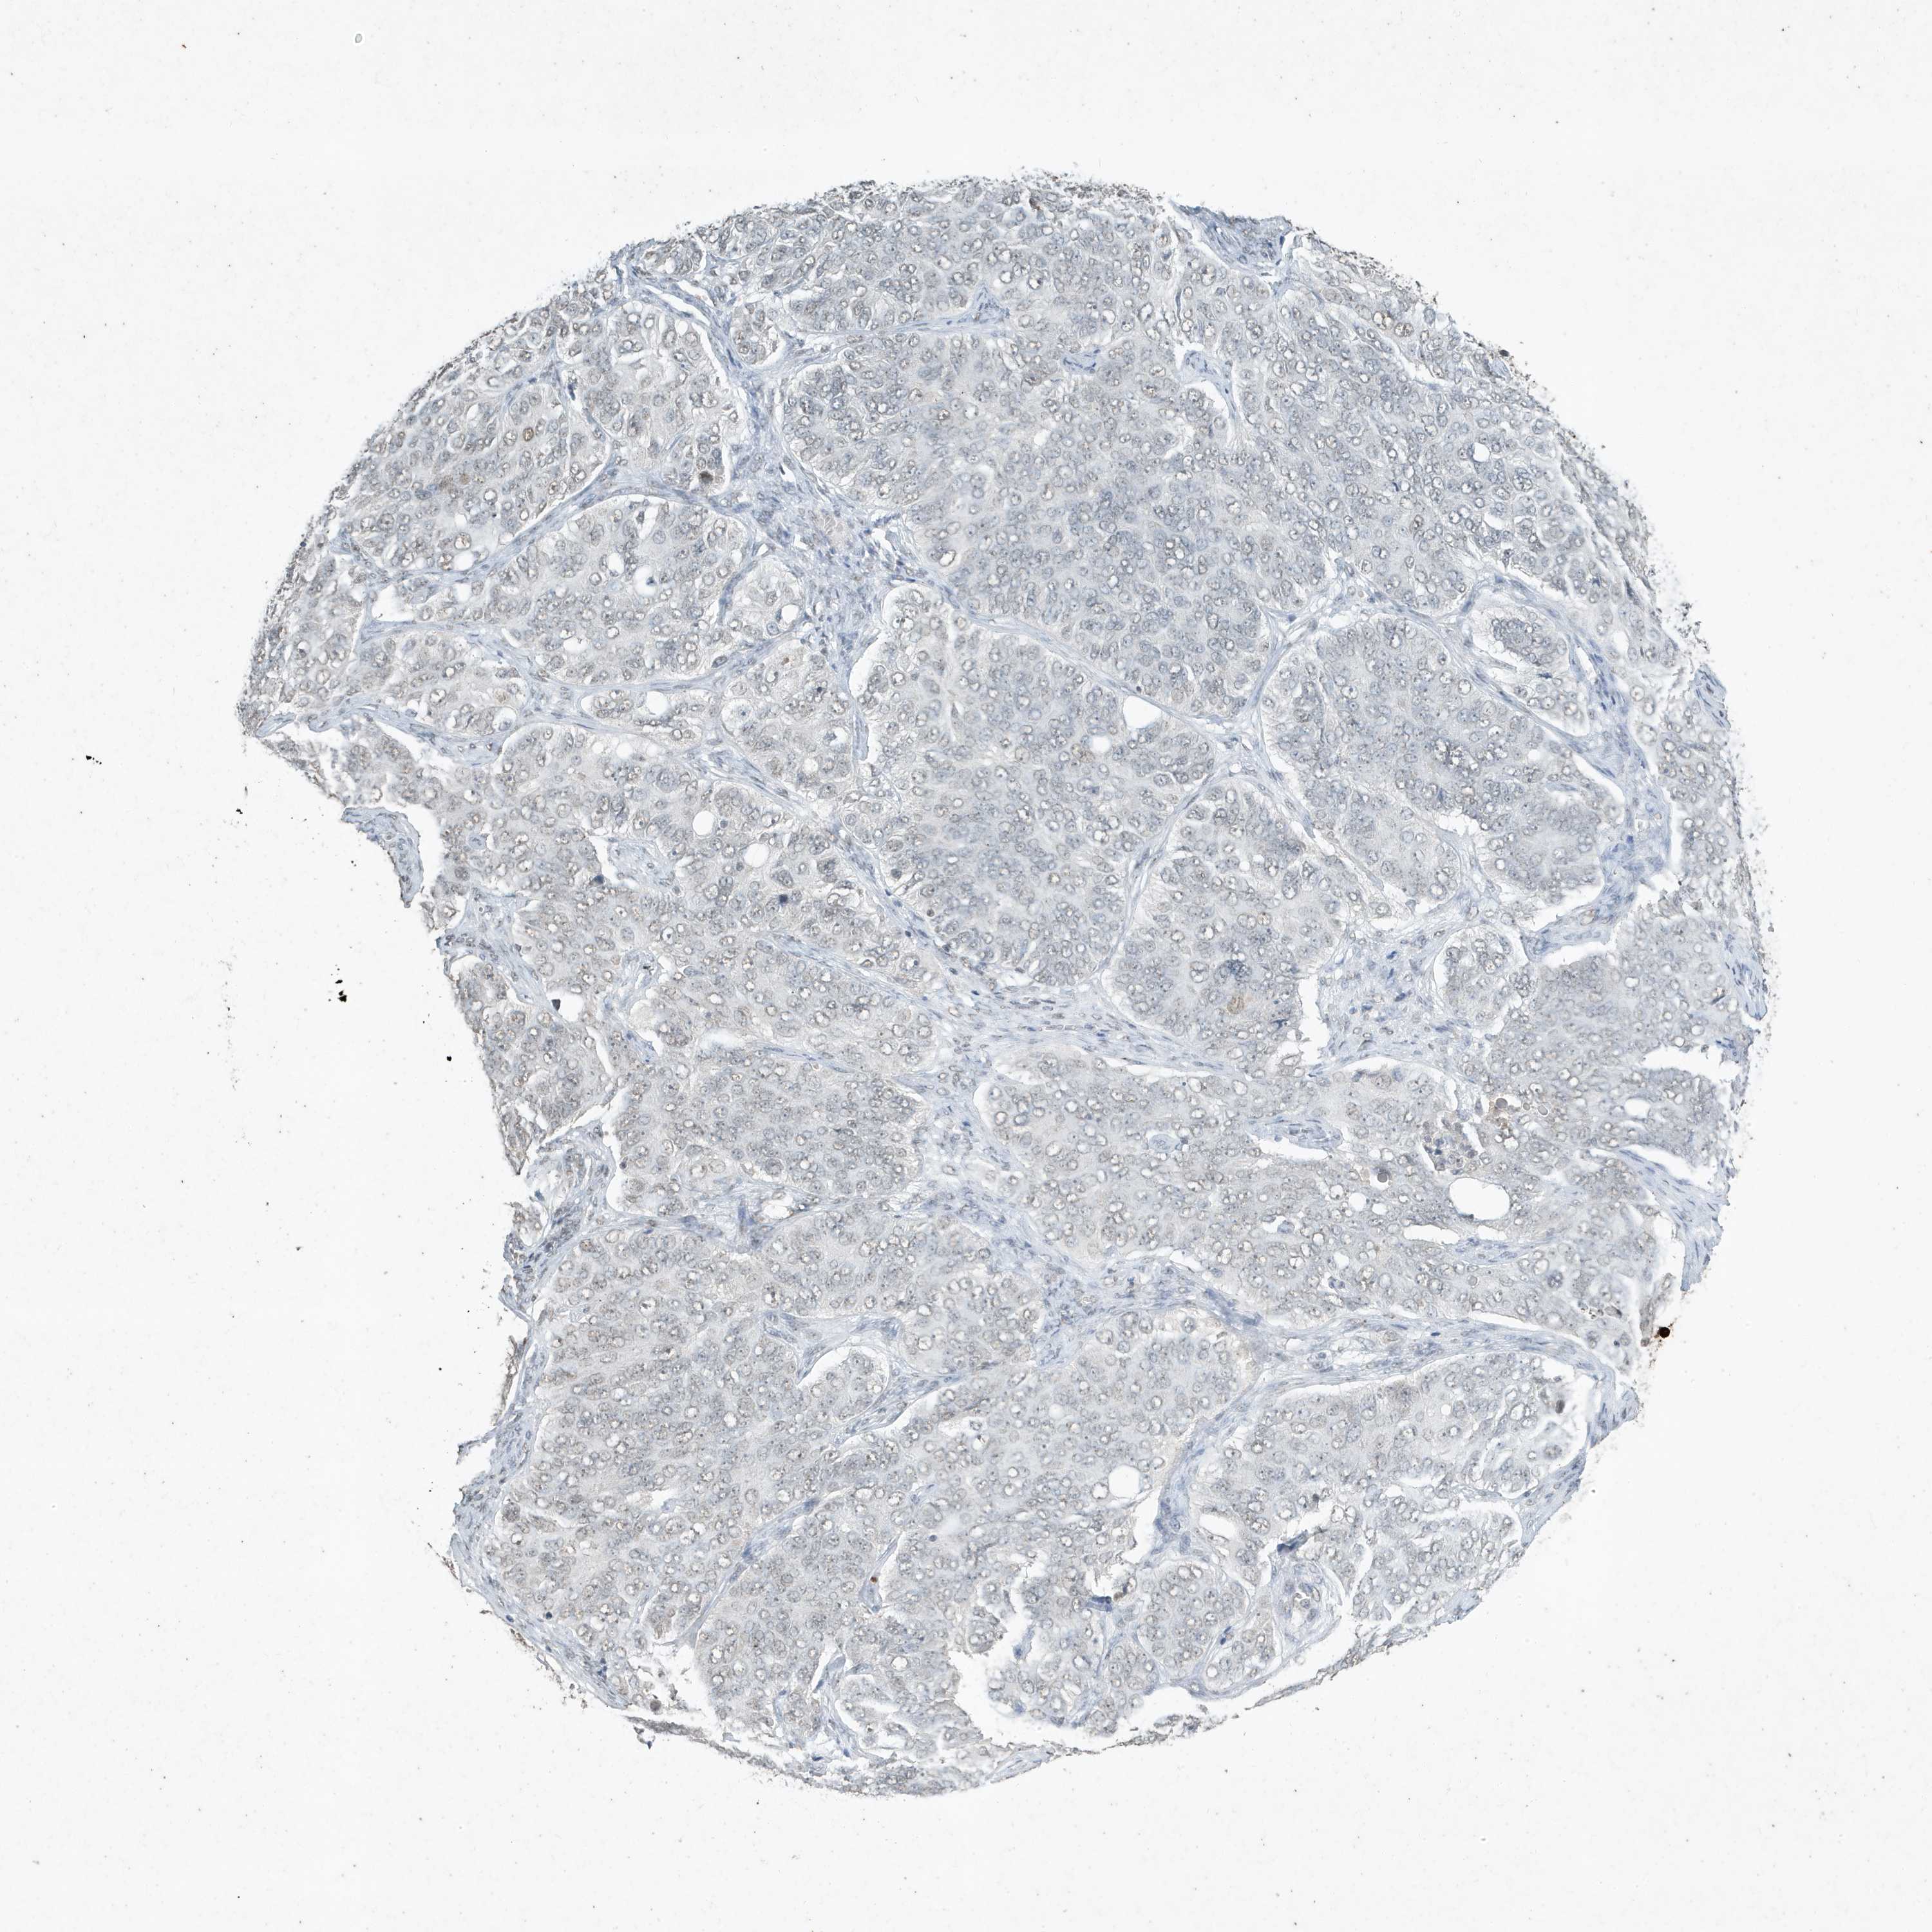

OVARIAN CANCER - Protein expressioni

A mouse-over function shows sample information and annotation data. Click on an image to view it in a full screen mode. Samples can be filtered based on level of antibody staining by selecting one or several of the following categories: high, medium, low and not detected. The assay and annotation is described here.

Note that samples used for immunohistochemistry by the Human Protein Atlas do not correspond to samples in the TCGA dataset.

Antibody stainingi

Antibody staining in the annotated cell types in the current human tissue is reported as not detected, low, medium, or high, based on conventional immunohistochemistry profiling in selected tissues. This score is based on the combination of the staining intensity and fraction of stained cells.

Each image is clickable and will lead to virtual microscopy that enables deeper exploration of all samples and also displays staining intensity scores, fraction scores and subcellular localization as well as patient and tissue information for each sample.

Antibody HPA052517

Antibody CAB032548

Staining

High

Medium

Low

Not detected

Intensity

Strong

Moderate

Weak

Negative

Quantity

>75%

75%-25%

<25%

None

Location

Nuclear

Cytoplasmic/membranous

Cytoplasmic/membranous,nuclear

Cystadenocarcinoma, serous, NOS

Cystadenocarcinoma, mucinous, NOS

Adenocarcinoma, NOS

Carcinoma, endometroid

Carcinoma, NOS